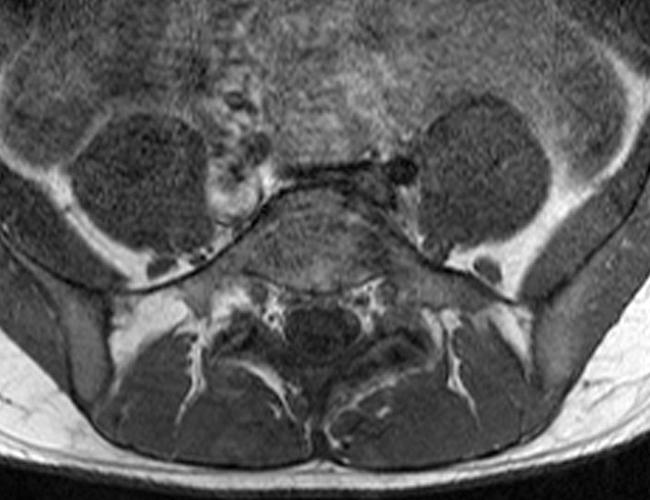

Case 2: 19-year-old male baseball player with acute onset of back pain after hitting a ball. Axial T1-weighted (2A) and T2-weighted (2B) images are provided. What are the findings? What is your diagnosis?

Case 2: T1-weighted (4A) and T2-weighted (4B) axial images show T1 hypointensity and T2 hyperintensity (arrowheads) in the left lamina of L5 adjacent to a small hypointense line (arrows) which traverses the lamina.

Case 2: Acute left-sided laminolysis